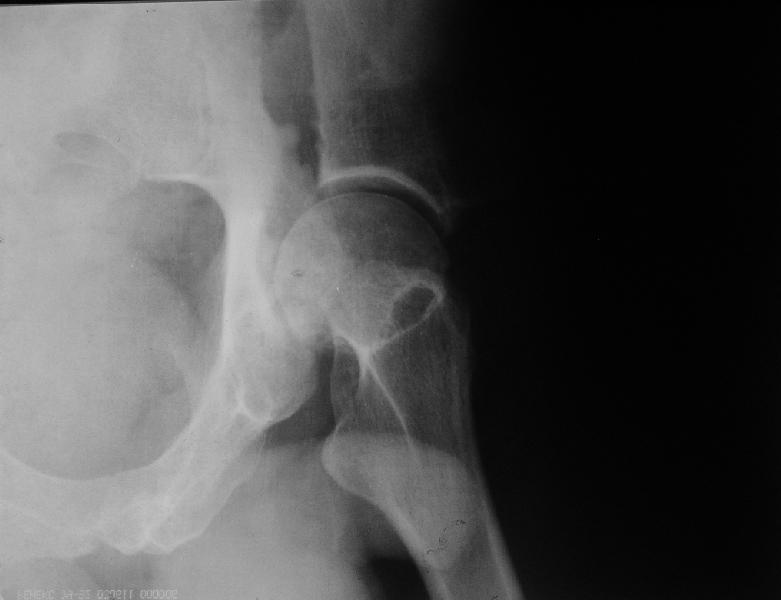

мужчина, 43 лет, получил травму в январе 2001 года. Лечился консервативно, в соседней области: скелетное вытяжение 6 недель, далее в кокситной гипсовой повязке 2 месяца. С декабря 2001 года ходит без дополнительной опоры, с компенсацией имеющегося укорочения - 4 сантиметра. С марта этого года беспокоят боли, усиливающиеся после умеренной физической нагрузки, возникающие в задних отделах таза и переходящие в область тазобедренного сустава. По данным ретгенографии и компьютерной томографии у больного имеется несросшийся высокий двухколонный перелом вертлужной впадины. Заранее спасибо.